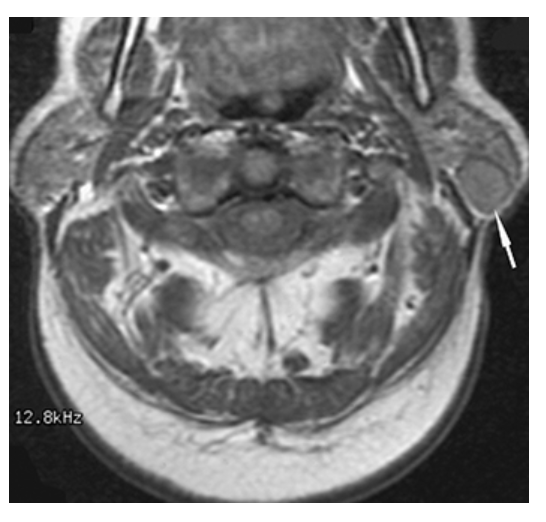

What does the figure show?

Parotid Gland Tumor. T1-weighted axial MRI of the parotid gland demonstrates a well-defined, round, low-signal intensity mass (arrow) in the posterior aspect of the superficial lobe of the left parotid gland.

Parotid Gland Mass. T2-weighted axial MRI of the parotid gland demonstrates a well-defined high-signal intensity mass (arrow) of the posterior aspect of the superficial lobe of the left parotid gland consistent with a pleomorphic adenoma.